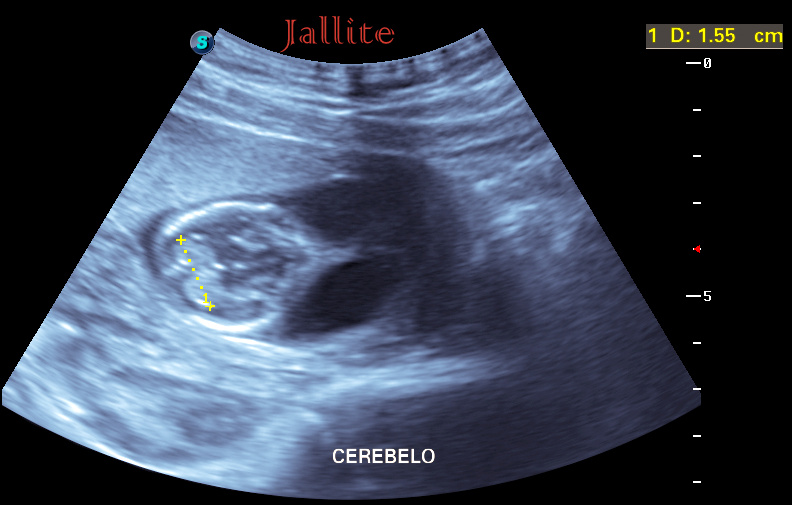

Recurrence: Isolated or part of Turner syndrome: no increased risk of recurrence. Part of autosomal recessive syndroms: 25%. The Fetal Medicine Foundation is a Registered Charity that aims to improve the health of pregnant women and their babies through research and training in fetal medicine.. Resumen . Objetivos: Determinar la importancia del espacio retronucal en fetos entre las 11 y 13+6 semanas, identificando sus características, la asociación con anomalías cromosómicas y las posibles diferencias entre higroma quístico y translucencia nucal aumentada.Diseño: Estudio transversal prospectivo.Institución: Instituto Latinoamericano de salud Reproductiva, Lima, Perú.

Ecografia 2D 11 semanas Higroma quistico pliegue nucal patologico Dr. Rafael Ortega Muñoz

HIGROMA QUISTICO MEDICINA FETAL PERÚ YouTube

Higroma quístico del primer trimestre Diagnóstico de hernia diafragmática congénita